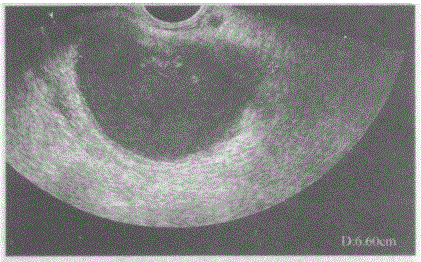

临床资料:女,27岁,自述月经期腹痛。临床物理检查:子宫右后方可扪及鸭蛋大肿块,压痛明显。超声综合描述:经阴道扫查左附件区可见6.6cm×6.1c...

问题 临床资料:女,27岁,自述月经期腹痛。 临床物理检查:子宫右后方可扪及鸭蛋大肿块,压痛明显。 超声综合描述:经阴道扫查左附件区可见6.6cm×6.1cm×4.6cm无回声区,边界清晰,形态规则,囊壁较厚,内透声不清亮,可见较密中强回声光点及光团浮动,CDFI:其内未见动静脉血流信号。 超声提示:

选项 A.左卵巢巧克力囊肿 B.左卵巢黄体囊肿 C.左输卵管积液 D.盆腔包裹性积液

答案 A